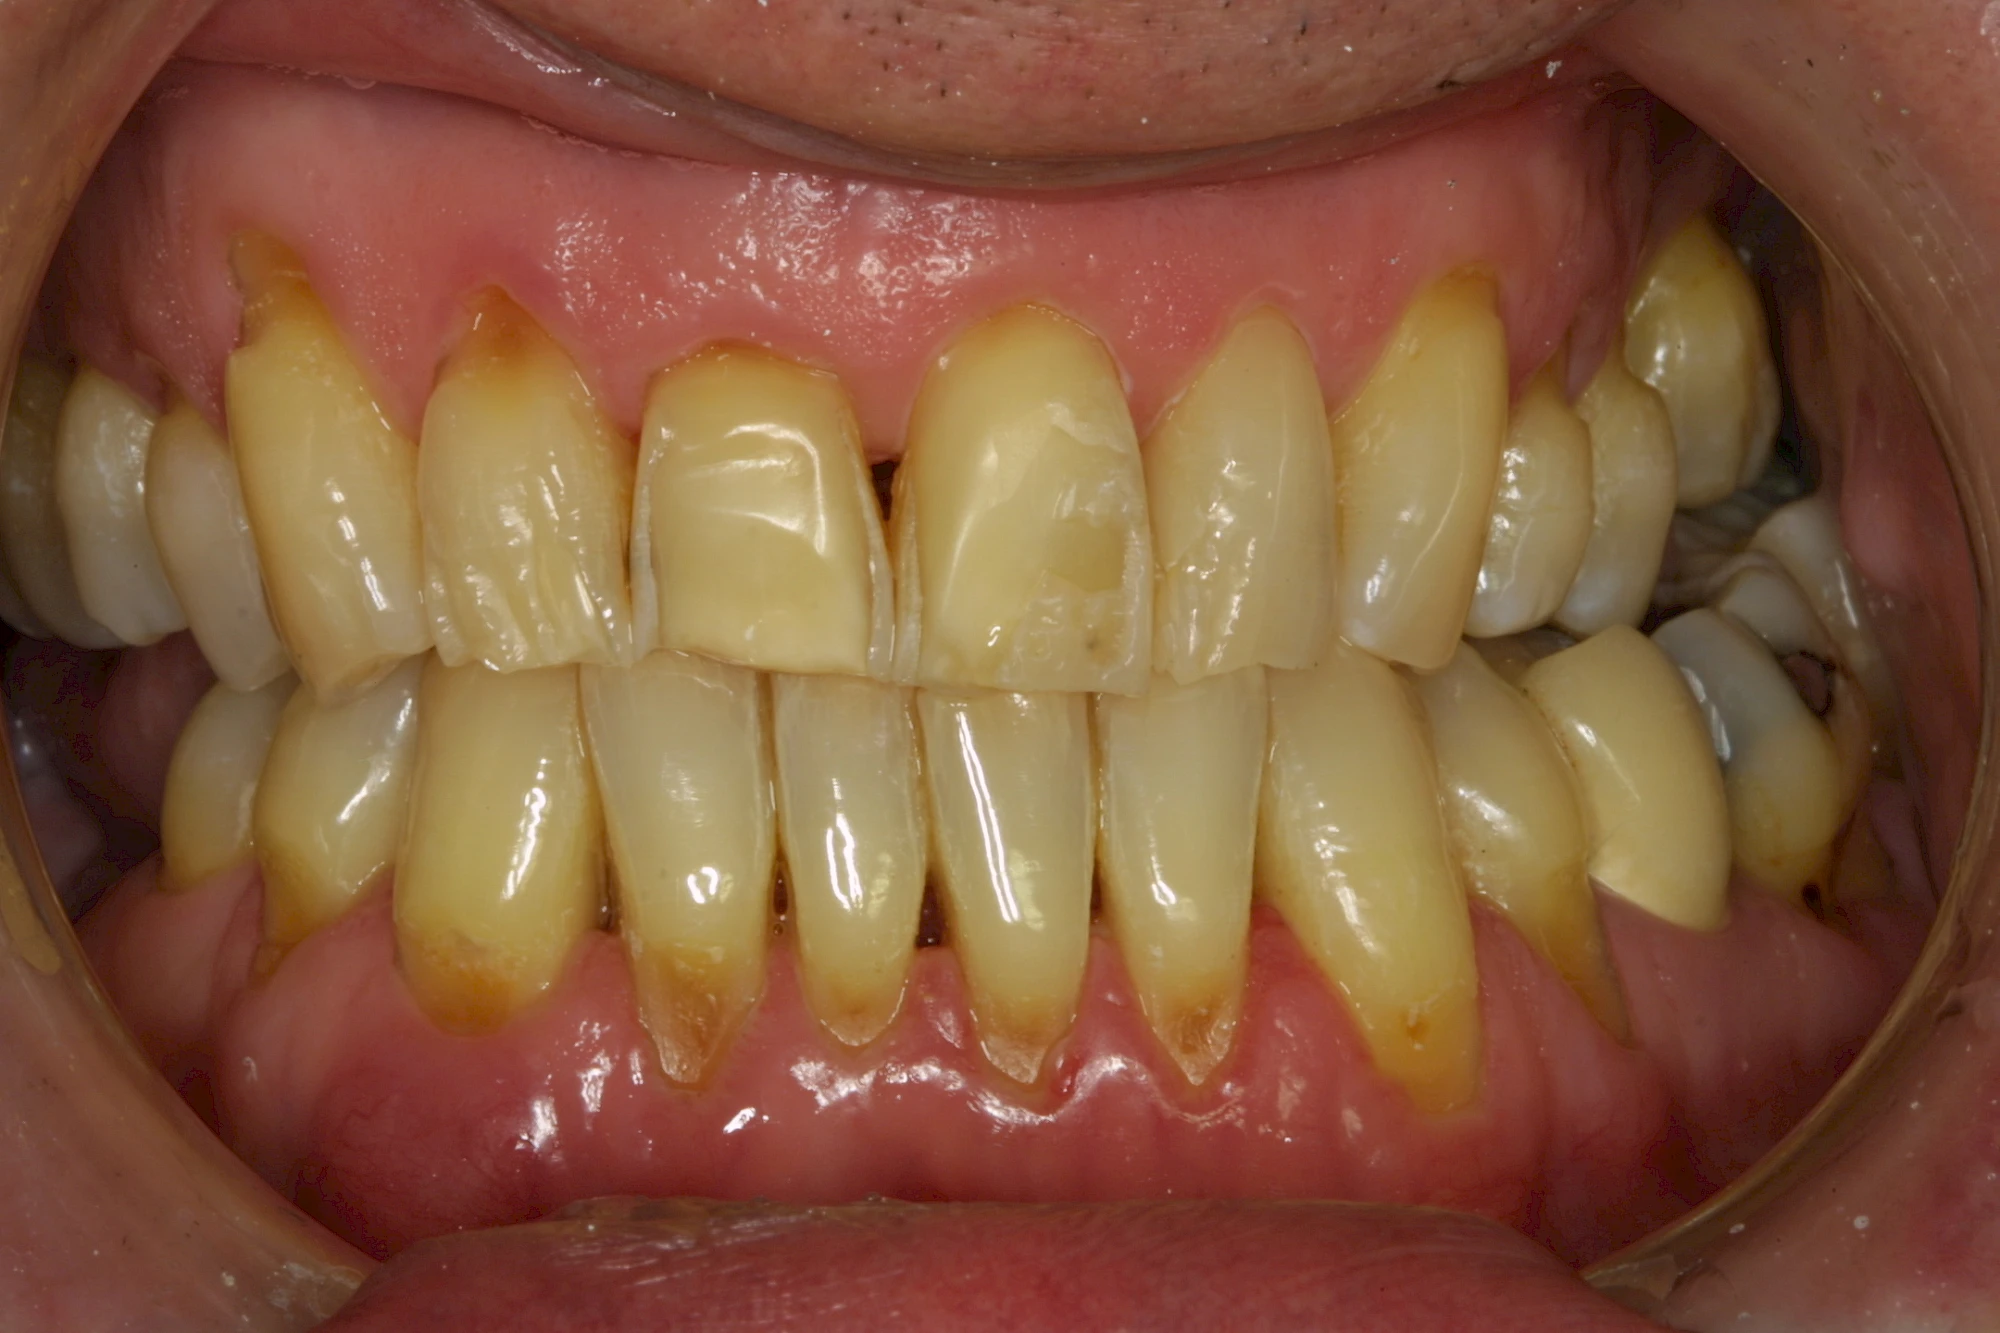

Über die Zeit können verschiedene Prozesse die Zahnhartsubstanzen aufzehren:

- Abnutzung durch Kauen (Abrasion) oder duch durch übermäßiges Knirschen bzw. Pressen (Attrition)

- Säurebedingte Auswaschung (Erosion)

- Knirschen bzw. Pressen und ungünstige Putztechnik (Druck): keilförmige Defekte